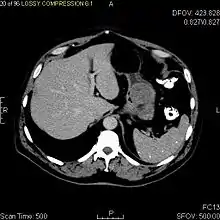

Large GISTs

As the tumor grows it may project outside the bowel (exophytic growth) and/or inside the bowel (intraluminal growth), but they most commonly grow exophytically such that the bulk of the tumor projects into the abdominal cavity. If the tumor outstrips its blood supply, it can necrose internally, creating a central fluid-filled cavity with bleeding and cavitations that can eventually ulcerate and communicate into the lumen of the bowel. In that case, barium swallow may show an air, air-fluid levels or oral contrast media accumulation within these areas.[14][17] Mucosal ulcerations may also be present. In contrast-enhanced CT images, large GISTs appear as heterogeneous masses due to areas of living tumor cells surrounding bleeding, necrosis or cysts, which is radiographically seen as a peripheral enhancement pattern with a low attenuation center.[13] In MRI studies, the degree of necrosis and bleeding affects the signal intensity pattern. Areas of bleeding within the tumor will vary its signal intensity depending on how long ago the bleeding occurred. The solid portions of the tumor are typically low signal intensity on T1-weighted images, are high signal intensity on T2-weighted images and enhanced after administration of gadolinium. Signal-intensity voids are present if there is gas within areas of necrotic tumor.[15][18][19]

Features of malignancy

Malignancy is characterized by local invasion and metastases, usually to the liver, omentum and peritoneum. However, cases of metastases to bone, pleura, lungs and retroperitoneum have been seen. In distinction to gastric adenocarcinoma or gastric/small bowel lymphoma, malignant lymphadenopathy (swollen lymph nodes) is uncommon (<10%) and thus imaging usually shows absence of lymph node enlargement.[13] If metastases are not present, other radiologic features suggesting malignancy include: size (>5 cm), heterogeneous enhancement after contrast administration, and ulcerations.[4][13][20] Also, overtly malignant behavior (in distinction to malignant potential of lesser degree) is less commonly seen in gastric tumors, with a ratio of behaviorally benign to overtly malignant of 3-5:1.[4] Even if radiographic malignant features are present, these findings may also represent other tumors and definitive diagnosis must be made immunochemically.